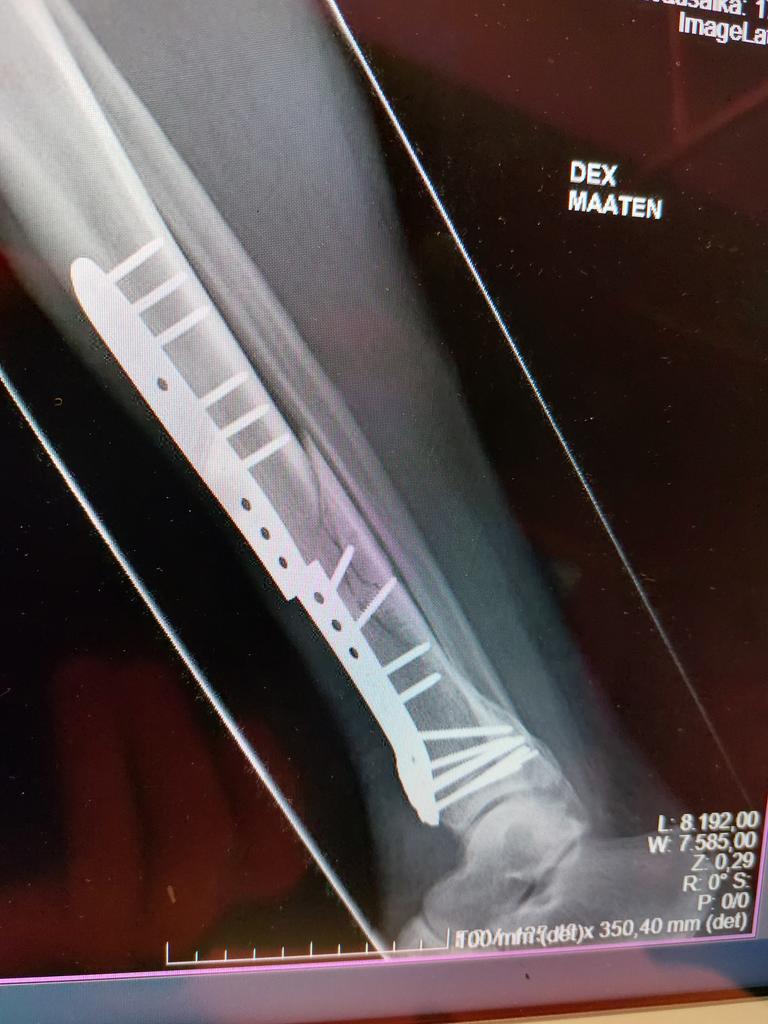

Rautaa ja ruuveja on kuin pienessä rautakaupassa... :mrgreen:

-Titaanilevy hajos ja katkaisi uudelleen melkein luutuneen sääriluun..... :shock:

-Nyt on "rautakankea", luulisi kestävän...? :?